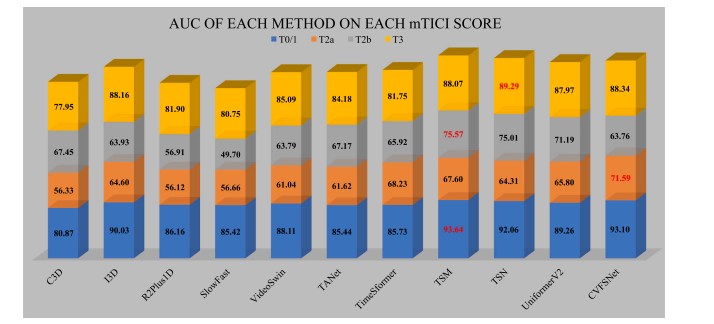

Fig. 8. AUC of each method on each mTICI score of AmTICIS, and best results are indicated in red

图8:在自动改良脑梗死溶栓分级评分(AmTICIS)数据集的每个mTICI评分等级上,各方法的曲线下面积(AUC),最优结果以红色标出。

We proposed a CVFSNet based on dual-view angiographic imagesfor automatic, objective, end-to-end mTICI scoring and built a crossview fusion module, CVFM, to integrate, aggregate, and complementfeatures from different views. In the ablation experiments, we firstcompared the performance between single-view and dual-view inputs,demonstrating the necessity of dual-view image input. This may bedue to the fact that DSA imaging is projection-compressed and intracranial vessel structures are complex, leading to vessel overlap insingle-view images, which affects the model’s ability to characterizeblood flow accurately. Then, by comparing different methods of dualview feature fusion, we verified the effectiveness of the CVFM module.CVFM leverages prior positional knowledge of coronal and sagittalviews, constructs oblique sagittal features using trigonometric functionsand the Pythagorean theorem, and employs a transformer-like moduleto explore complementary relationships between coronal and sagittalfeatures, thereby building global dependencies and generating more expressive fused features, ultimately enhancing performance. In the comparative experiments, we compared our approach with some classicaland state-of-the-art video feature classification models, demonstratingsuperior performance andgood stability.In the dichotomized experiments, CVFSNet demonstrated performance exceeding 90% across all indicators, implying that CVFSNet mayhave the potential for clinical application in determining the adequacyof mTICI scores. However, our study also has limitations. Firstly, thesevideo feature classification methods that were compared in the comparative experiments only supported single-view inputs, which maydisadvantage their comparison in terms of performance. Additionally,the AmTICIS dataset constructed in this study only includes data forM1 segment stenosis, limiting its clinical applicability. In the future,we plan to expand the dataset to include more mTICI scoring datawith various vessel stenosis, such as Internal Carotid Artery (ICA), BaseArtery (BA), Anterior Cerebral Artery (ACA), and Posterior CerebralArtery (PCA) etc., thereby constructing a more comprehensive scoringdataset. Also, the sample size of AmTICIS can be further expanded byincorporating data from multiple centers to enhance its diversity.In conclusion, we propose a novel CVFSNet in this paper for automatic, objective, and end-to-end mTICI scoring. Specifically, CVFSNetemploys dual branches to simultaneously extract spatial–temporal features from coronal view and sagittal view, and these cross-view featuresare fused through a novel cross view fusion module that explores thepositional characteristics of coronal and sagittal views to fuse andgenerate a pseudo-oblique sagittal feature and deploys a transformerlike architecture to explore the correlation between different viewfeatures, ultimately constructing more representative features to enhance the scoring performance of the model. In addition, we providea newly collected and the first publicly available digital subtractionangiography image dataset with expert annotations (AmTICIS) for automatic mTICI scoring, which can effectively promote researchers toconduct studies of ischemic stroke based on DSA images and finallyhelp patients get better medical treatment. Extensive experimentationresults demonstrate the promising performance of our methods and theeffectiveness of the cross-view fusion module.

我们基于双视角血管造影图像提出了CVFSNet网络,用于实现自动、客观、端到端的脑梗死溶栓治疗改良分级(mTICI)评分,并构建了一个跨视角融合模块(CVFM),以整合、聚合和补充来自不同视角的特征。在消融实验中,我们首先比较了单视角输入和双视角输入的性能,结果表明了双视角图像输入的必要性。这可能是因为数字减影血管造影(DSA)成像是投影压缩的,且颅内血管结构复杂,导致单视角图像中出现血管重叠,从而影响了模型准确表征血流的能力。然后,通过比较不同的双视角特征融合方法,我们验证了CVFM模块的有效性。CVFM利用冠状面和矢状面的先验位置知识,使用三角函数和勾股定理构建斜矢状面特征,并采用类似Transformer的模块来探索冠状面和矢状面特征之间的互补关系,从而建立全局依赖关系,并生成更具表现力的融合特征,最终提升性能。在对比实验中,我们将我们的方法与一些经典的以及最先进的视频特征分类模型进行了比较,结果显示出我们的方法具有优越的性能和良好的稳定性。 在二分类实验中,CVFSNet在所有指标上的表现均超过了90%,这意味着CVFSNet在确定mTICI评分是否足够方面可能具有临床应用潜力。然而,我们的研究也存在局限性。首先,在对比实验中所比较的这些视频特征分类方法仅支持单视角输入,这在性能比较方面可能对它们不利。此外,本研究构建的AmTICIS数据集仅包含大脑中动脉M1段狭窄的数据,限制了其临床适用性。未来,我们计划扩展该数据集,纳入更多具有各种血管狭窄情况的mTICI评分数据,例如颈内动脉(ICA)、基底动脉(BA)、大脑前动脉(ACA)和大脑后动脉(PCA)等,从而构建一个更全面的评分数据集。同时,通过纳入多个中心的数据来进一步扩大AmTICIS的样本量,以提高其多样性。 总之,本文提出了一种新颖的CVFSNet网络,用于自动、客观、端到端的mTICI评分。具体而言,CVFSNet采用双分支同时从冠状面和矢状面提取时空特征,并且这些跨视角特征通过一个新颖的跨视角融合模块进行融合。该模块探索冠状面和矢状面的位置特征,以融合并生成伪斜矢状面特征,并部署了类似Transformer的架构来探索不同视角特征之间的相关性,最终构建出更具代表性的特征,以提升模型的评分性能。此外,我们提供了一个新收集的、首个带有专家注释的公开可用的数字减影血管造影图像数据集(AmTICIS),用于自动mTICI评分,这可以有效地推动研究人员基于DSA图像开展缺血性中风的研究,并最终帮助患者获得更好的治疗。大量的实验结果证明了我们方法的良好性能以及跨视角融合模块的有效性。

Table 4Quantitative comparison of the scoring performance of different methods on AmTICIS. † indicates significancy (𝜌 < 0.05). Best results are indicated in bold.

表4:在自动改良脑梗死溶栓分级评分(AmTICIS)数据集上,不同方法的评分性能的定量比较。†表示具有显著性((\rho < 0.05))。最优结果以粗体显示。